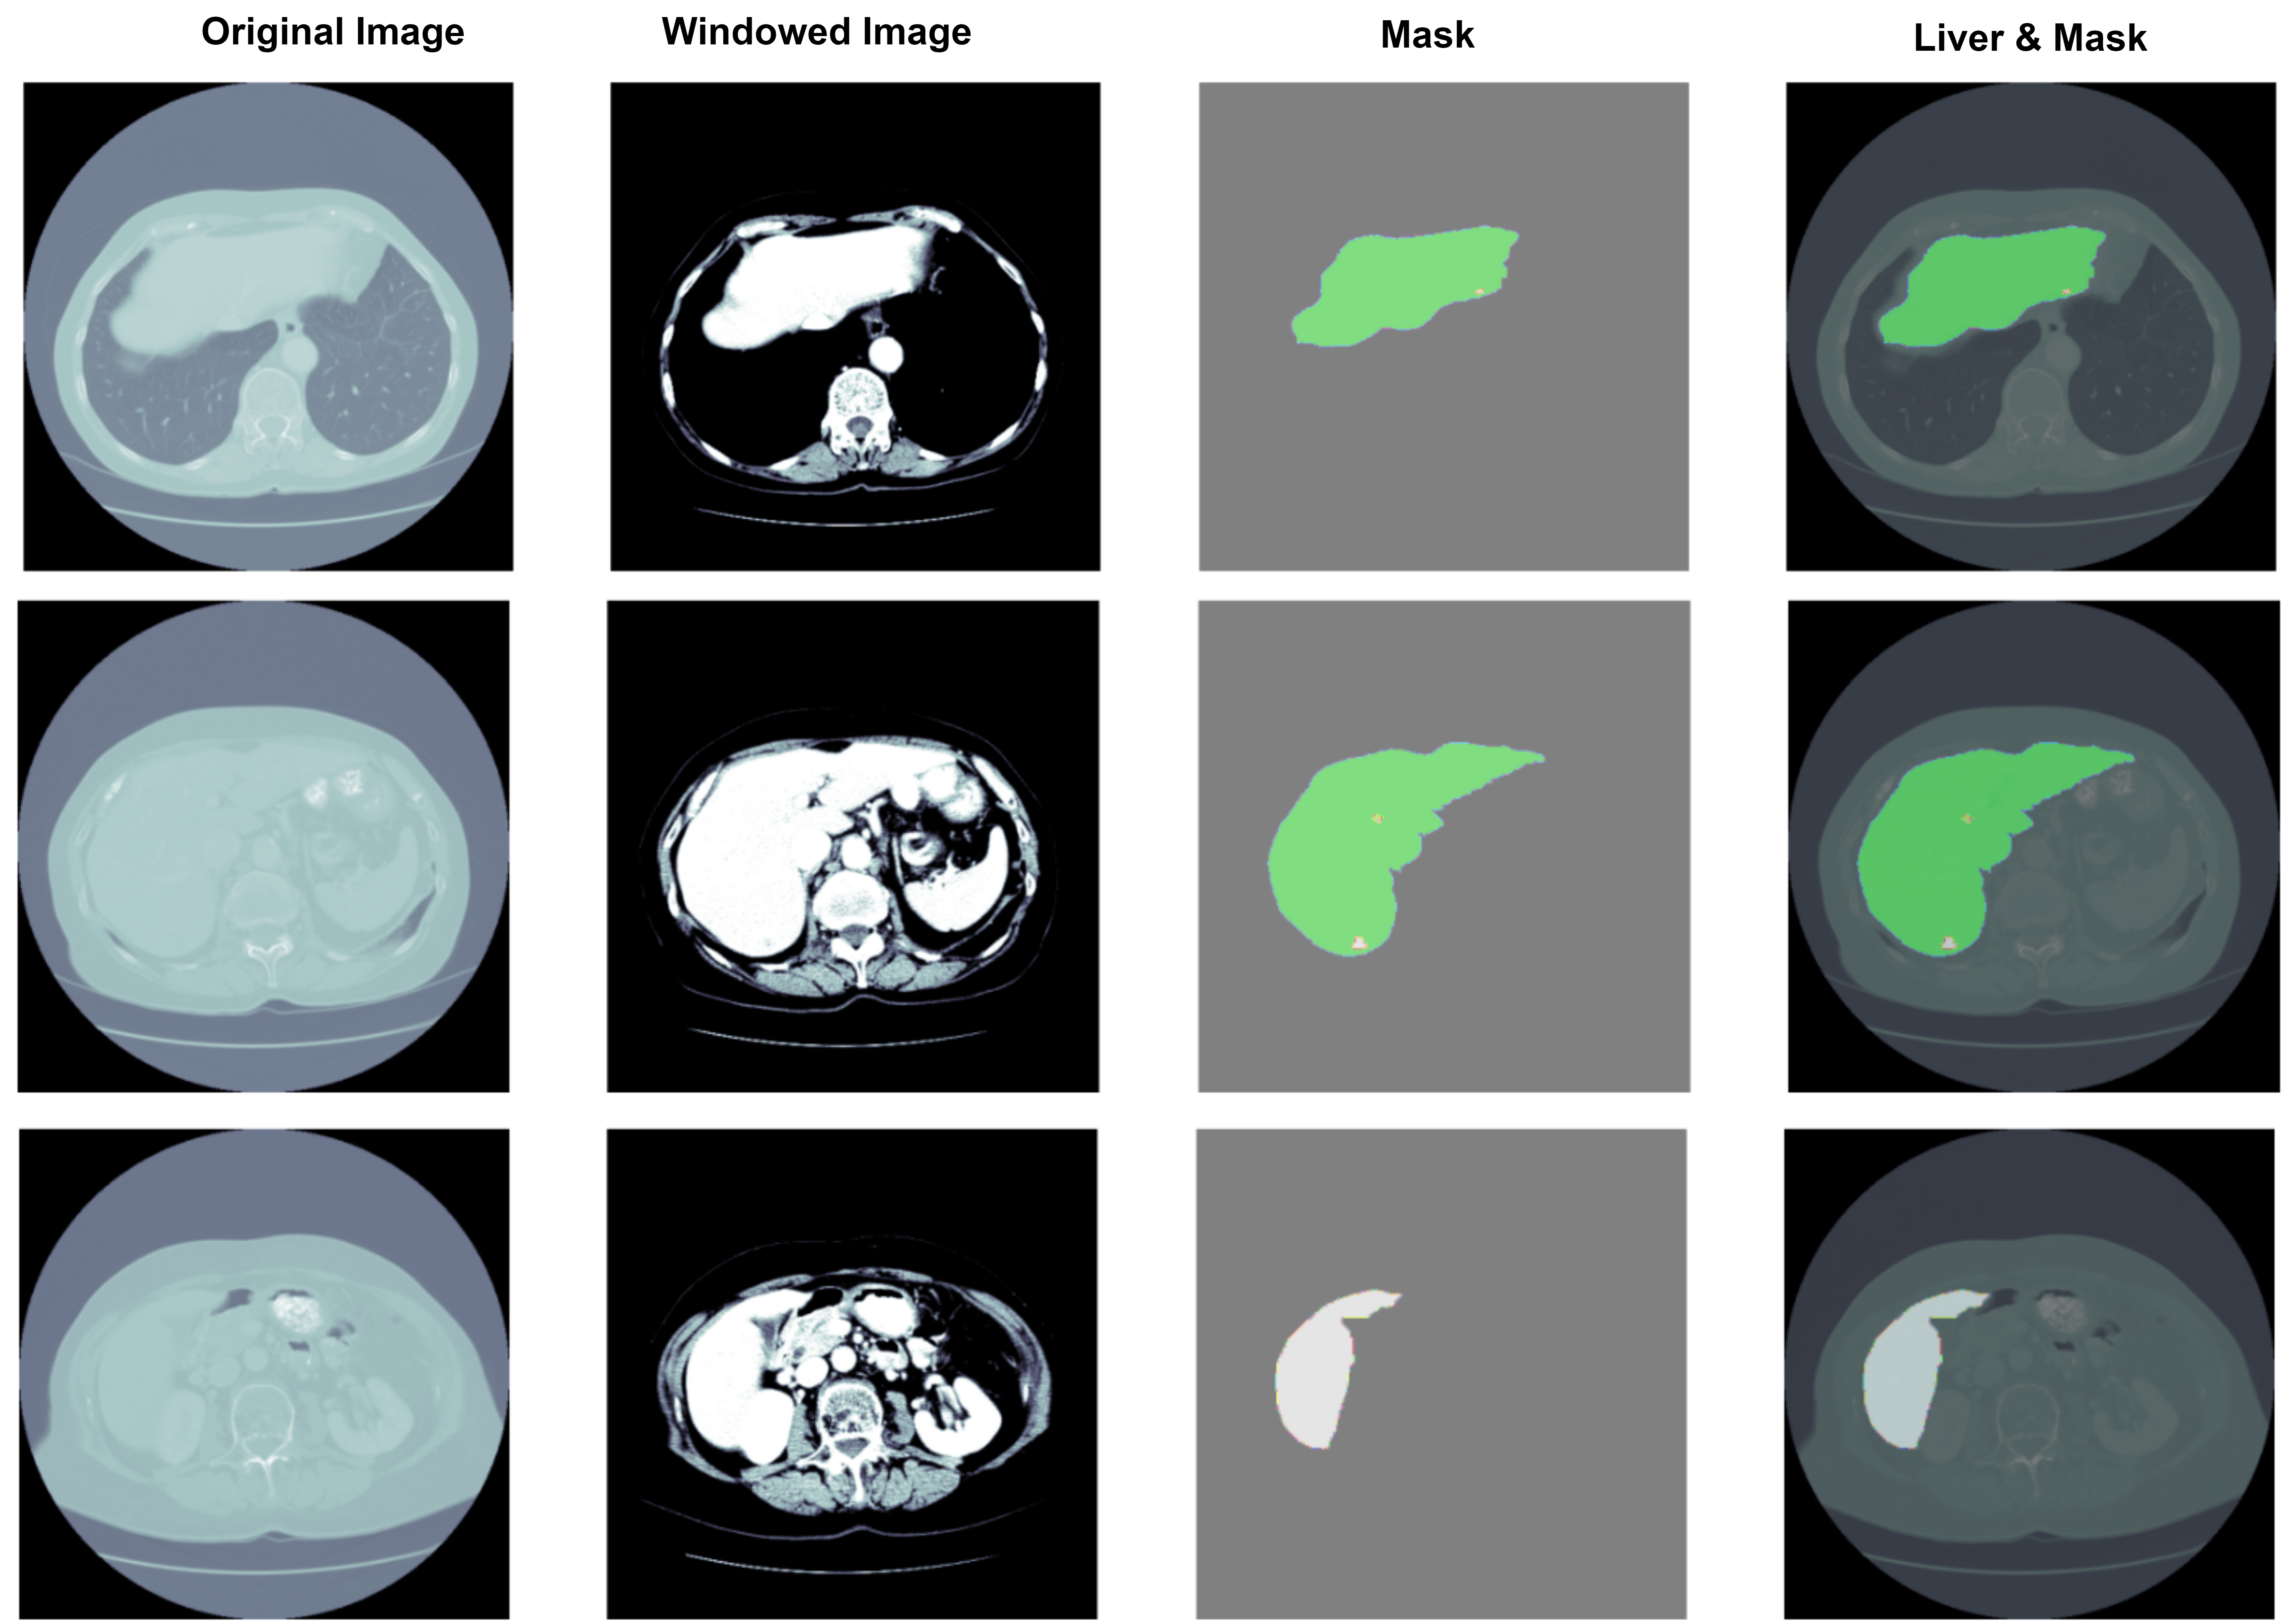

Refer to caption

Figure 3: Sample images and respective annotations from the Liver dataset [34]

The liver dataset used in this study was sourced from the Kaggle platform [35] and consists of 130 CT scans for segmenting both the liver and tumor lesions. For this study, the tumor labels were merged with the liver labels to simplify the problem into a binary classification task. This dataset is part of the Liver Tumor Segmentation Challenge (LiTS17), organized in conjunction with ISBI 2017 and MICCAI 2017. The data and segmentations were provided by multiple clinical sites globally, ensuring diversity and robustness in the dataset. Figure.3 shows sample images from the liver dataset. The Swin UNET [27] model was employed for liver segmentation. This advanced semantic segmentation framework combines the strengths of the Swin Transformer and the UNet architecture to address the challenges of 3D medical image segmentation. The Swin Transformer backbone processes the input volumes through hierarchical stages, effectively capturing long-range dependencies and multi-scale contextual information with its shifted window approach. This ensures that both global context and fine details are incorporated in the segmentation process. This is integrated with UNet’s ability to maintain spatial localization through skip connections, which link corresponding encoder and decoder layers. The decoder then reconstructs high-resolution segmentation maps by combining the detailed spatial information from these skip connections with the hierarchical features from the encoder. This synergy between global context captured by the Swin Transformer and the precise spatial details from UNet enables SwinUnet to achieve superior segmentation performance on complex volumetric medical datasets, effectively balancing broad contextual understanding with fine-grained local delineation.